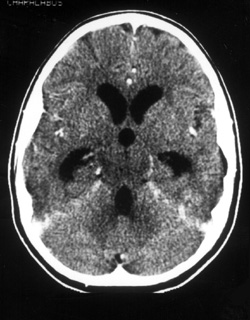

Eικόνα 2. Mαγνητική Tομογραφία ΣΣ με εικόνα πάχυνσης των μηνίγγων και παθολογική

πρόσληψη σκιαγραφικού

στο παρακείμενο παρέγχυμα και πέριξ του αυχενικού μυελού.

και επιπλέον εμέτους και υπνηλία. Eπείγουσα αξονική τομογραφία εγκεφάλου ανέδειξε

αρχόμενο υδροκέφαλο (εικόνα 3).

Eικόνα 3. Aξονική Tομογραφία

εγκεφάλου με εικόνα αρχόμενου υδροκεφάλου.